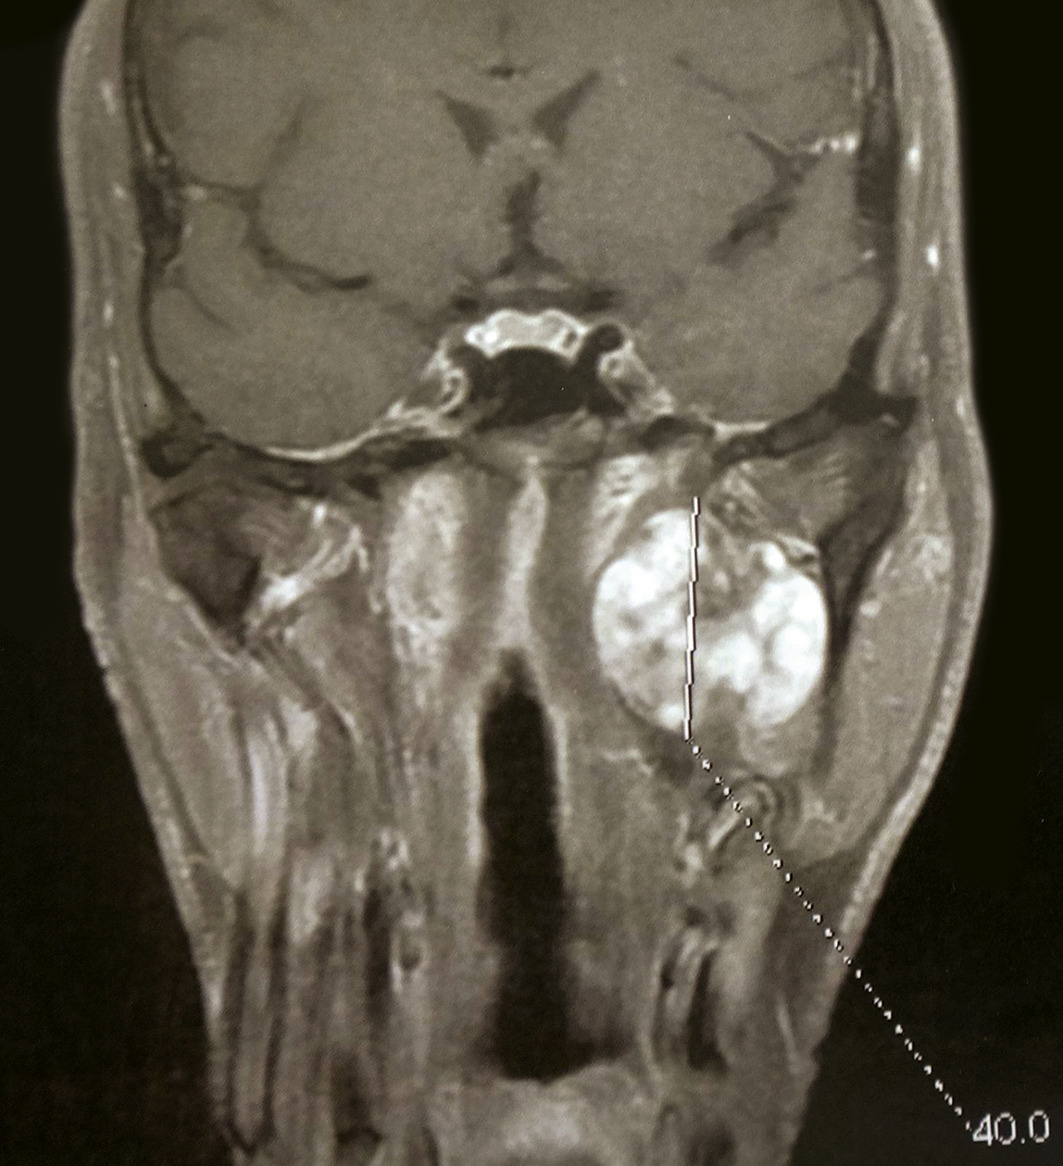

L’IRM est l’examen de référence. Elle permet de mettre en évidence des tumeurs de petite taille, d’affirmer la nature paro­tidienne de la masse et parfois de localiser le nerf facial par rapport à la tumeur. Elle offre en outre une orientation diagnostique (séquences de perfusion-diffusion) :

• adénome pléomorphe : hypersignal T2, polylobé, unifocal ;

• cystadénolymphome : kystique, multifocal, régulier ;

• tumeur maligne (carcinome adénoïde kystique) : masse infiltrante à limites irrégulières.